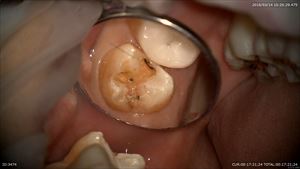

MTAセメントで封鎖して型とりしました。